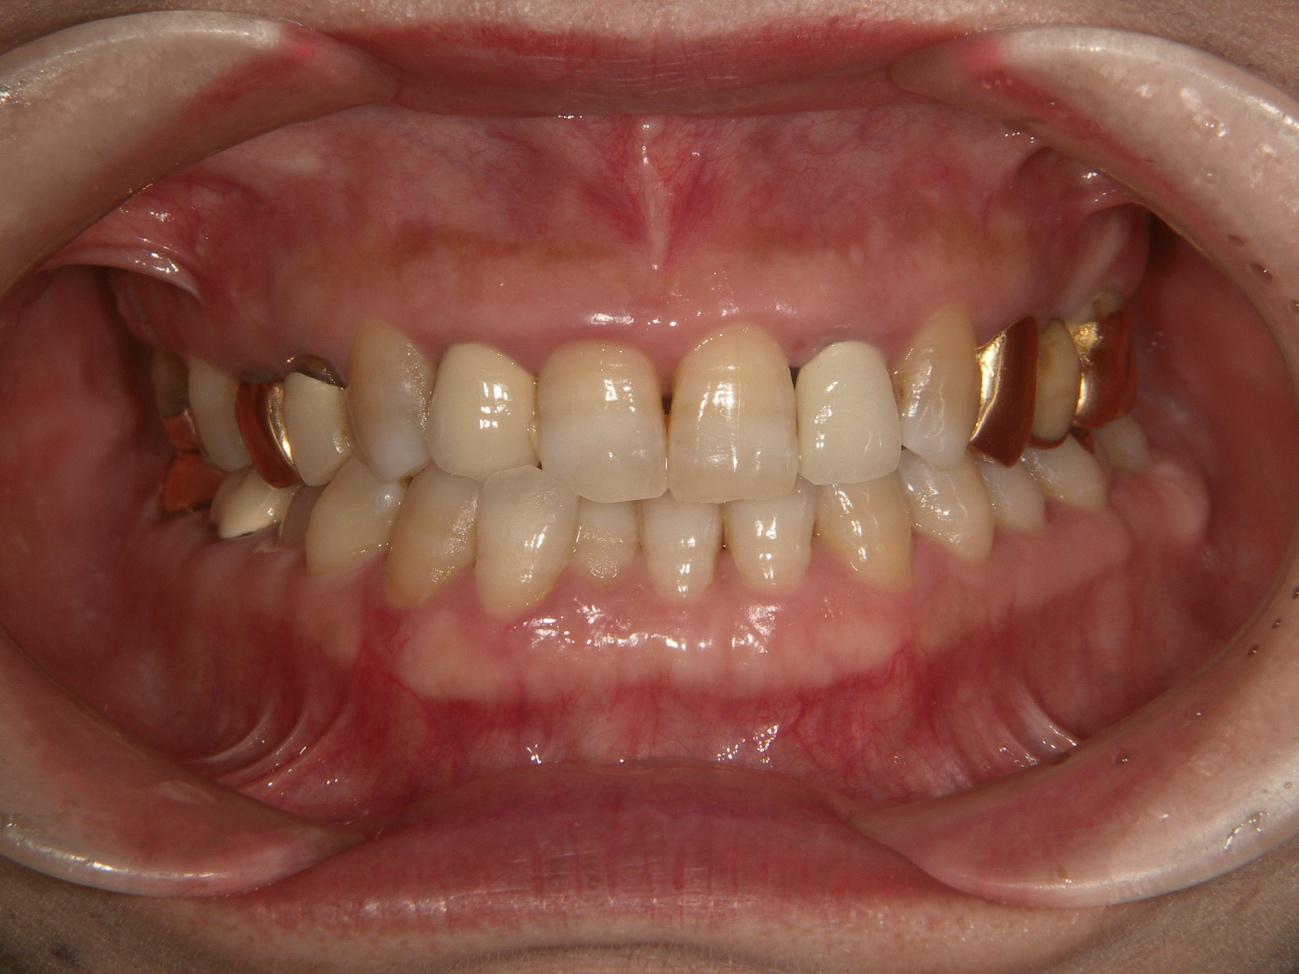

患者様のお悩み

歯茎が痛くて物が食べれない

治療法・使用素材

オールセラミック インプラント

患者様の年代

70

治療開始年齢

73

治療にかかった期間

2年半

性別

女性

この治療のリスクについて

糖尿病の悪化による歯周状態の悪化

治療にかかった費用

400万

治療前

治療後